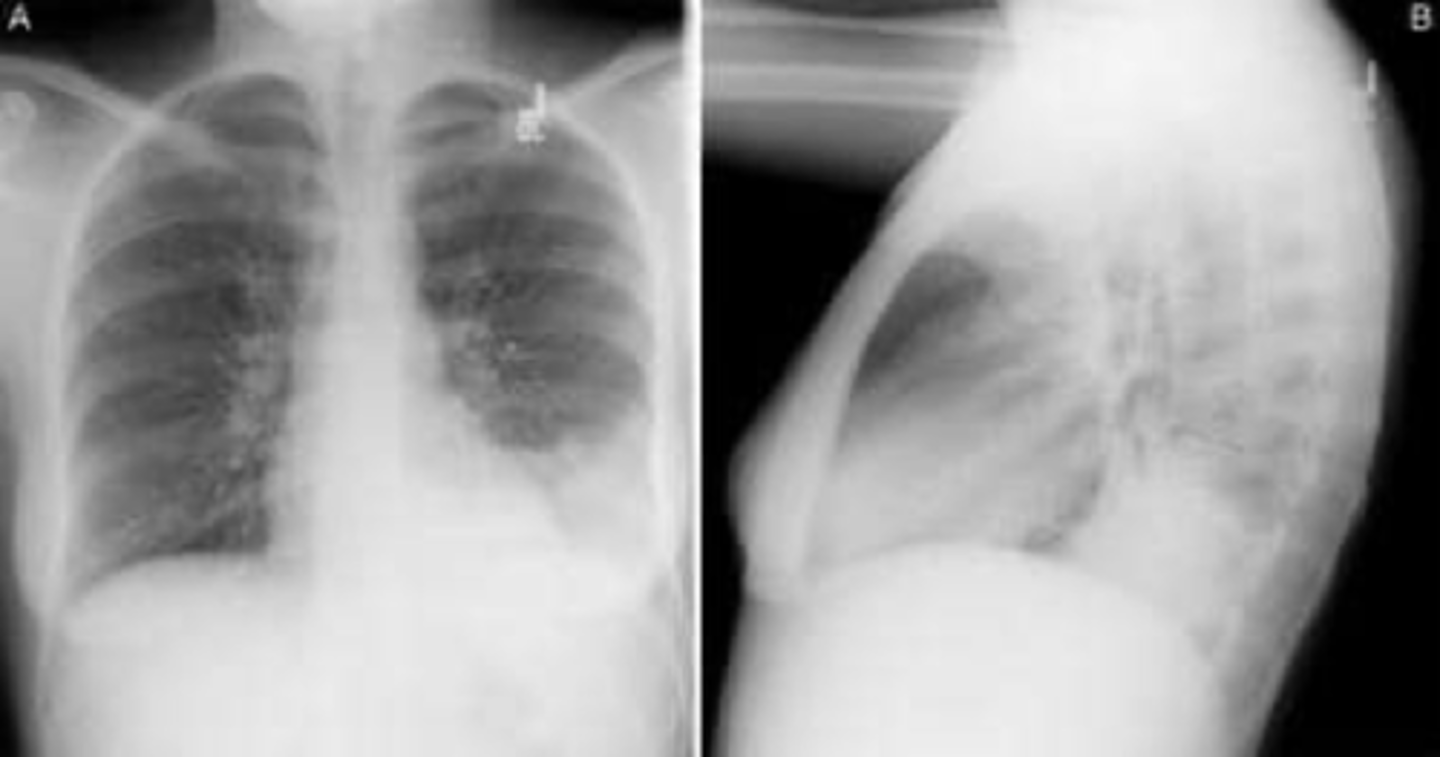

air bronchogram- alveolar consolidation LUL